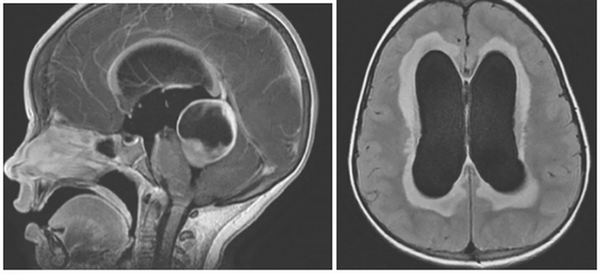

![Гидроцефалия на МРТ]()

Внутренняя тривентрикулярная окклюзионная гидроцефалия на МРТ во фронтальной и сагиттальной плоскостях: на левом снимке видно гигантское кистозно-солидное образование, явившееся причиной обструкции ликворопроводящих путей на уровне Сильвиева водопровода